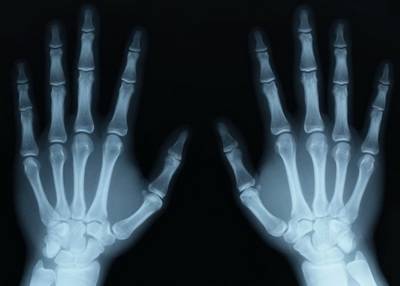

X Ray Cihazı (Almanya'da keşfedildi)

19. yy'da Alman bilim adamı Wilhelm Conrad Röntgen radyasyon ile deney yaparken kemiklerin göründüğünü keşfetti.